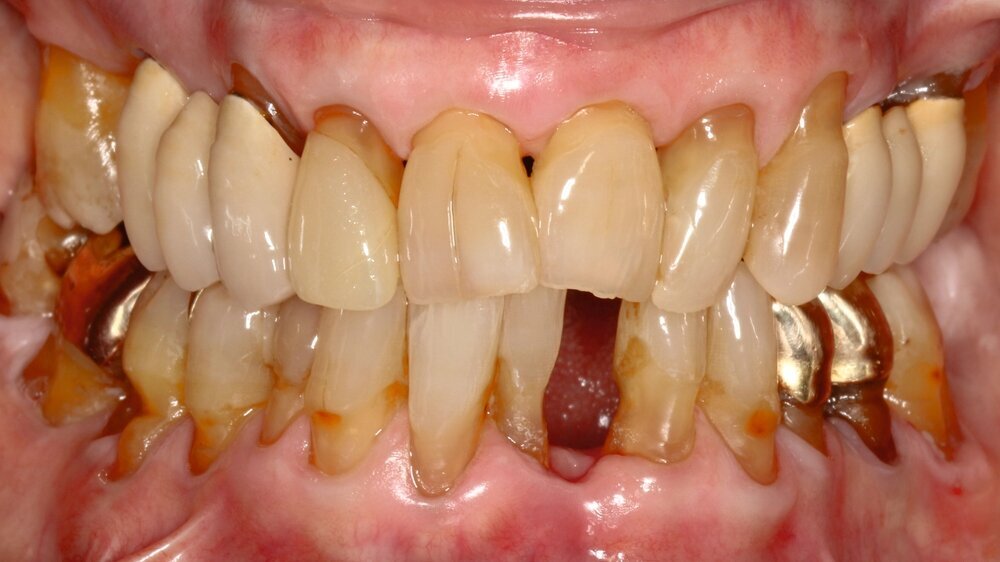

Die hochbetagte Patientin war bereits viele Jahre in der Poliklinik für Zahnerhaltung des Universitätsklinikums Tübingen zahnmedizinisch betreut worden, allerdings aus Sorge vor einer Corona-Infektion von Ende 2019 bis August 2023 knapp vier Jahre der zahnärztlichen Versorgung ferngeblieben. Grund der Wiedervorstellung war dann ein wenige Tage zuvor stattgefundener Füllungsverlust am Zahn 36. Hier bemerkte die Patientin eine an der Zunge störende scharfkantige Fraktur des Molaren (Abbildungen 2 und 3). Weitere Schmerzen oder Beschwerden gab sie nicht an. Im Rahmen der zahnärztlichen Untersuchung konnten multiple Rezessionen und diverse arretierte Brown-Spot-Läsionen festgestellt werden.

Obwohl die unterstützende Parodontitistherapie (UPT) vier Jahre unterbrochen war, konnte bis auf einen Grad III gelockerten Zahn 31 und eine Grad I–II gelockerte, restliche Unterkieferfrontbezahnung ein gut erhaltenes Gebiss festgestellt werden. Dies ist auch darauf zurückzuführen, dass die Patientin – trotz ihres fortgeschrittenen Alters – die häusliche Mundhygiene stets sehr gründlich betrieb, wie auch aus früheren Akteneinträgen ersichtlich wurde (Abbildung 4).